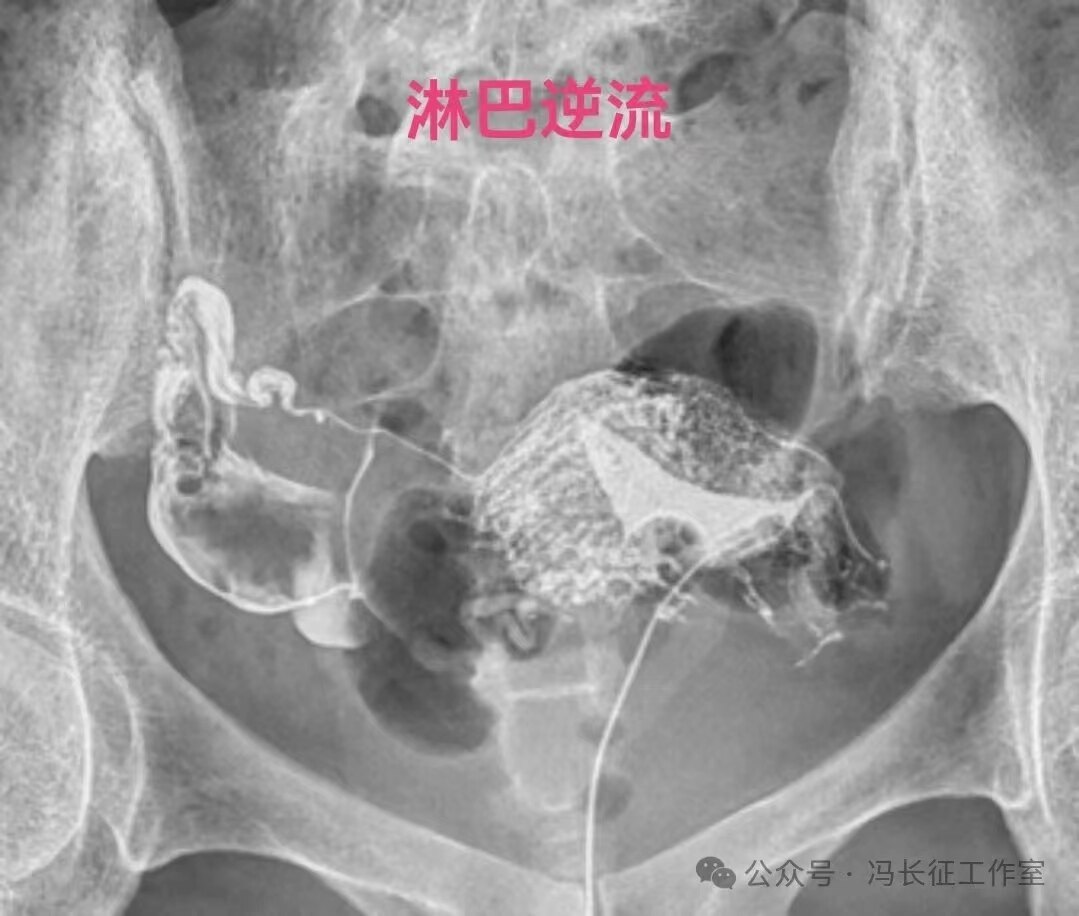

造影剂逆流可以进入静脉和淋巴管,逆流分三种:(1)淋巴逆流;(2)静脉逆流;(3)淋巴和静脉混合性逆流。其实,一般多是静脉和淋巴都有的混合性逆流,淋巴逆流是造影当时以淋巴逆流为主,同时有少量的静脉逆流,本来淋巴管后来就是要汇入到静脉的。静脉逆流也是以静脉逆流为主,同时有少量的淋巴逆流。